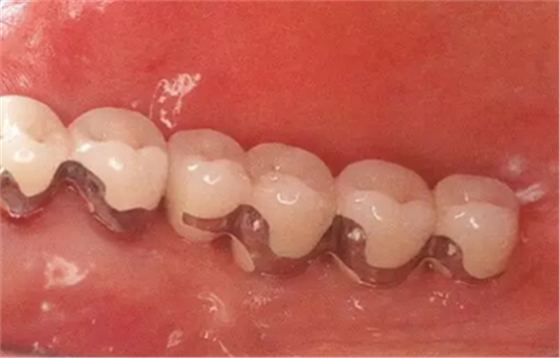

▲圖10-9,10

頰舌側(cè)都獲得了充足的角化齦,菌斑控制狀態(tài)良好。

▲圖10-11,12

佩戴最終修復(fù)體后2年的狀態(tài)。頰舌側(cè)角化齦寬度均充足。